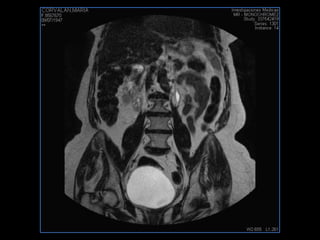

PROTOCOLO pelvis SAG T2, Y FAT SAT (FINOS) AXIAL T1  AX FAT SAT CON   GADOLINIO :  AX T1 Y COR T1 SAT: NO  FASE: RL THK: 3MM  COIL:  GAP: (FACTOR 1.4) 1MM FOV: 40 CM NEX:2 SINCRONIZACION RESPIRATORIA EN 3 O 4 CICLOS ALE

resonancia de abdomen